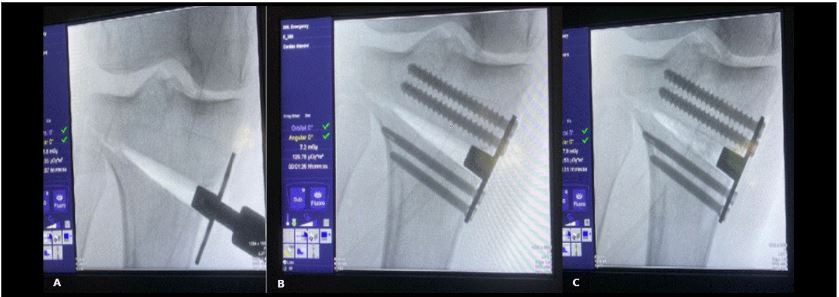

Mediante una incisión oblicua en cara anteromedial de la pierna se expuso la cara medial del tercio proximal de la tibia y liberación del ligamento colateral medial. Posteriormente, bajo visión directa con el intensificador de imágenes, se colocó una clavija desde medial, con dirección al tercio superior de la articulación tibioperonea proximal para marcar la localización del corte de la osteotomía (Fig. 2). Se realizó luego una osteotomía incompleta, que en el plano sagital debe ser paralela al slope tibial y sin afectar la cortical lateral de la tibia. Se inició el corte con sierra oscilante y se finalizó mediante escoplos. Luego de esta última, se procedió a su apertura gradual (Fig. 3). Una vez lograda la corrección planificada, se colocó una placa tipo Puddu, con los dos tornillos proximales para esponjosa, de 6.5 mm de diámetro y dos tornillos distales bloqueados, de 4.5 mm de diámetro (todas las placas fueron fabricadas en Argentina). Fijada adecuadamente la osteotomía, se rellenó la brecha de apertura con injerto óseo autólogo o alógeno liofilizado, mezclado con 1 g de vancomicina en polvo (Fig. 4). La colocación de la placa lo más cercana a la cortical posterior de la tibia tiene por objetivo tratar de evitar el incremento del slope tibial (Fig. 5).

Figura 3.Uso de escoplos para finalizar la osteotomía y apertura progresiva de la brecha

Figura 4.Colocación de la placa tipo Puddu. A) Apertura y mantenimiento de la brecha con placa y su pedestal. B) Fijación de la placa con dos tornillos proximales de esponjosa de 6.5 mm de diámetro y dos tornillos distales de 4.5 mm bloqueados. C) Relleno de la brecha con injerto óseo